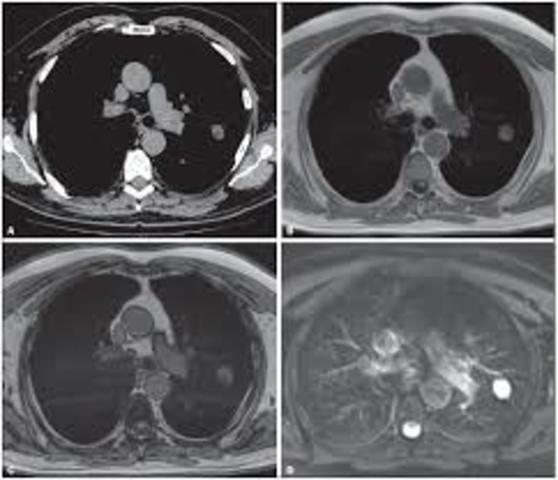

El británico Godfrey Newbold Hounsfield presenta en Londres el primer tomógrafo computarizado, en el cual la imagen no es analógica, como en la radiología convencional, sino digital.

Raymond Damadian Vahan fue el primero en realizar una exploración completa del cuerpo de un ser humano en 1977 para diagnosticar el cáncer. Damadian inventó un aparato y método para el uso de RMN con seguridad y precisión para explorar el cuerpo humano, un método ahora conocido como la resonancia magnética.